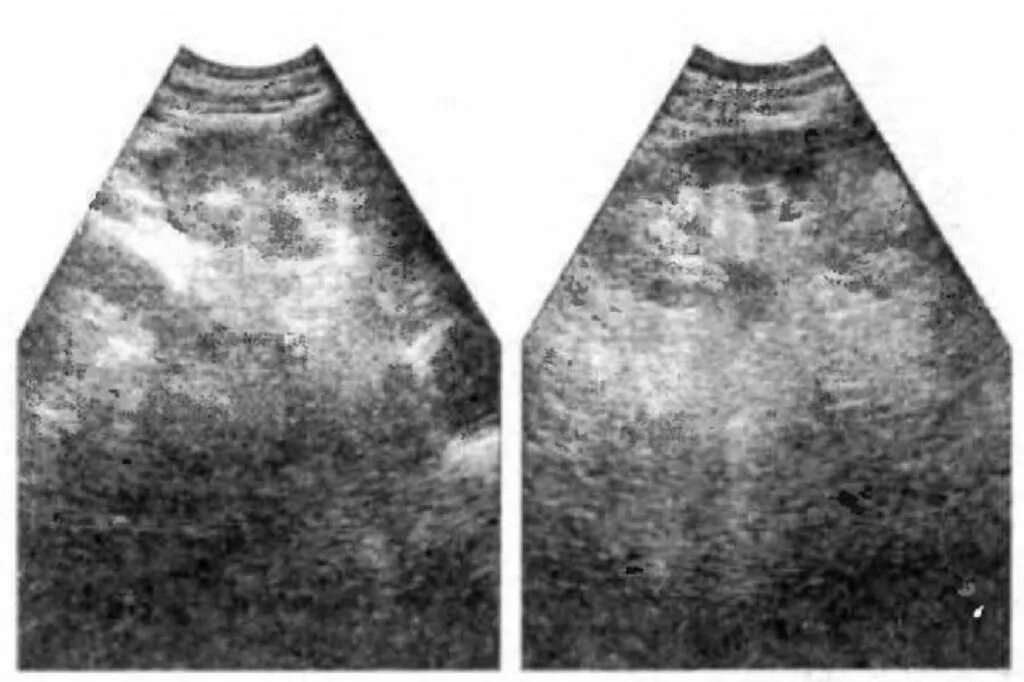

Диффузное изменение почек у ребенка